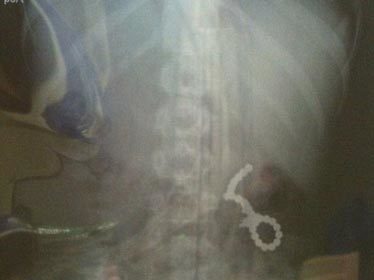

Ảnh: Các viên nam châm trong dạ dày bé trai (Ảnh: Dailymail) |

Các bác sĩ đã so sánh các vết thương mà cậu bé phải chịu cũng giống như các vết thương do đạn bắn, mặc dù các viên nam châm mà cậu nuốt phải rất nhỏ.

"Khi chơi khối nam châm, thằng bé ngậm nó vào miệng và vô tình nuốt phải. Các viên nam châm đã dính vào nhau ở trong ruột con trai tôi. Hiện tại, nó phải ăn uống bằng cách dùng một ống thông nối với dạ dày. Xin đừng mua cho con bạn những thứ đồ chơi như vậy. Nếu con bạn có nó, bạn phải ném nó đi thật xa" - cô Denise cho biết.